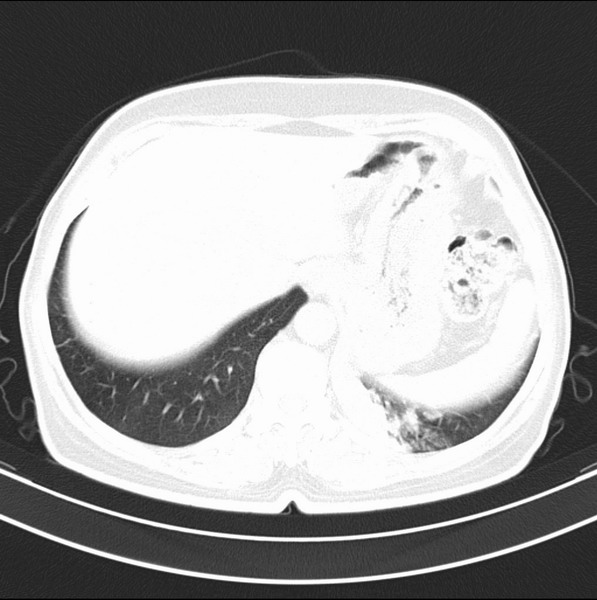

女、63

咳嗽、胸痛四个月

支持左下中央型肺癌伴阻塞性炎症不张。

包绕左下肺基底段的不规则的软组织肿块,段支气管腔变形、狭窄及阻塞性炎症,病变区不规则强化,又是老年女性支持楼上看法。

考虑左肺下叶中央型肺癌伴阻塞性肺炎、支气管黏液嵌塞。

典型病例:左下肺基底段中央型肺癌,相应支气管狭窄并阻塞性炎症